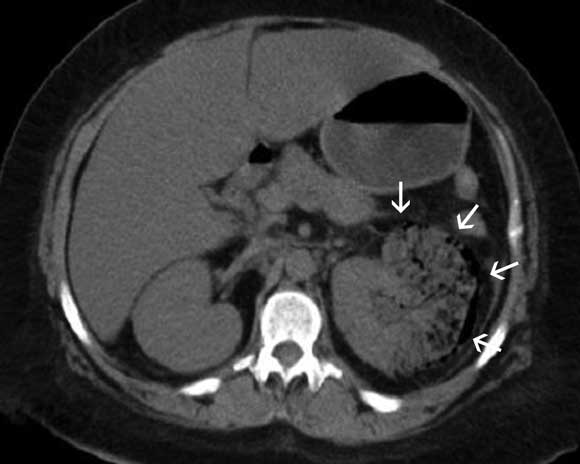

A 40-year-old Indigenous woman with type 2 diabetes presented with a 6-month history of intermittent left flank pain. She reported worsening pain of 2 days’ duration associated with fever, nausea, vomiting and reduced urine output. Clinical examination revealed tenderness over the left loin. An x-ray (not shown) and computed tomogram of the abdomen (Box) suggested a diagnosis of emphysematous pyelonephritis.

Emphysematous pyelonephritis is a rare, severe gas-forming infection of the renal parenchyma, typically seen in people with diabetes. Radiologically, four classes of emphysematous pyelonephritis are described on computed tomography:1 in Class 1 and 2, the gas is localised to the collecting system and the renal parenchyma, respectively, without extension to the extrarenal space; in Class 3A, as seen in this case, there is extension of gas or abscess into the perinephric space, and in Class 3B, to the pararenal space; bilateral emphysematous pyelonephritis or emphysematous pyelonephritis of a solitary kidney represents the most severe form of the disease (Class 4).